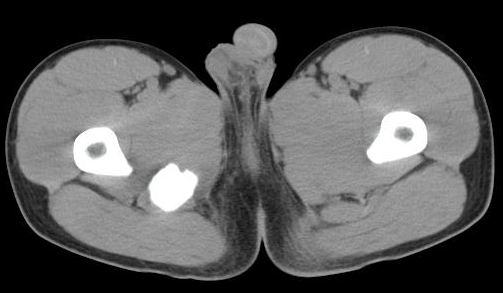

男性,15岁,半年前曾有做运动摔伤史,伤后左肢麻木,一天后恢复,两个月后因右臀部隐痛照片示右坐骨下骨性密度影,现复查见骨性影无明显改变。求助诊断!

支持坐骨撕脱性骨折合并血肿机化、骨化。

坐骨骨折,血肿机化

右骨折伴骨化性肌炎

应该没有骨折,骨化性肌炎.